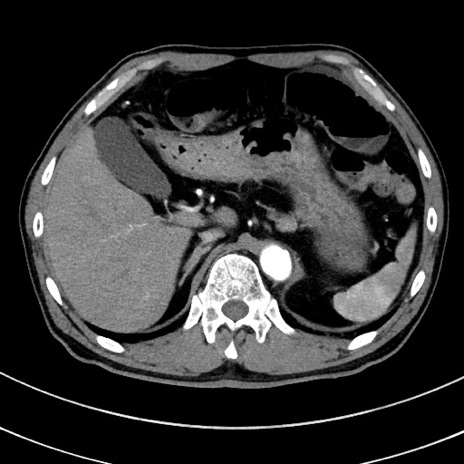

冠状断像

【症例】 60歳代男性

【主訴】 黒色吐物

【現病歴】 4日前から嘔気自覚、2日前の朝食後にも嘔気あり、自分で手で嘔吐反射起こし嘔吐したところ血が混ざっていたため受診。

【既往歴】 5年前汎発性腹膜炎を伴う急性虫垂炎で手術、高血圧、前立腺肥大症、高脂血症

【身体所見】 腹部正中に手術癩痕あり 腹部平坦・軟圧痛なし膨満感あり

【データ】WBC 8400、CRP 4.54